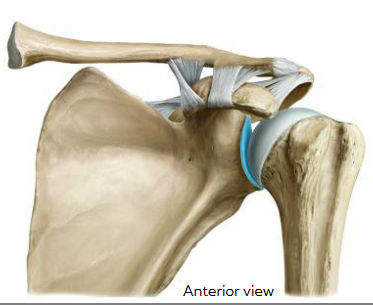

Label the 3 parts of the synovial joint

Left: Articular cartilage (hyalin)

Right top: Synovial Cavity ( filled w/ synovial fluid)

Right bottom: Joint capsule (fibrous and synovial membrane)